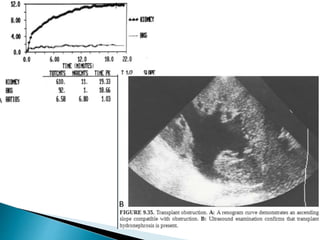

1. Urinary leak

3. Ureteral obstruction

URTERAL OBSTRUCTION